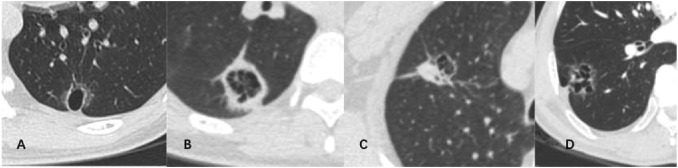

1. 根据Mascalchi等的研究,囊腔型肺癌在CT下可分为四种模式(见图1)。

图1. I-IV型示意图

• I型:囊性气腔外实性结节

• II型:囊性气腔内实性结节

• III型:囊性气腔伴弥漫性囊壁增厚

• IV型:多个囊性气腔,内有实性和/或非实性组织。该特殊类型是以贴壁样(lepidic)为主的腺癌、微小浸润性腺癌和原位腺癌中所常见的典型模式。